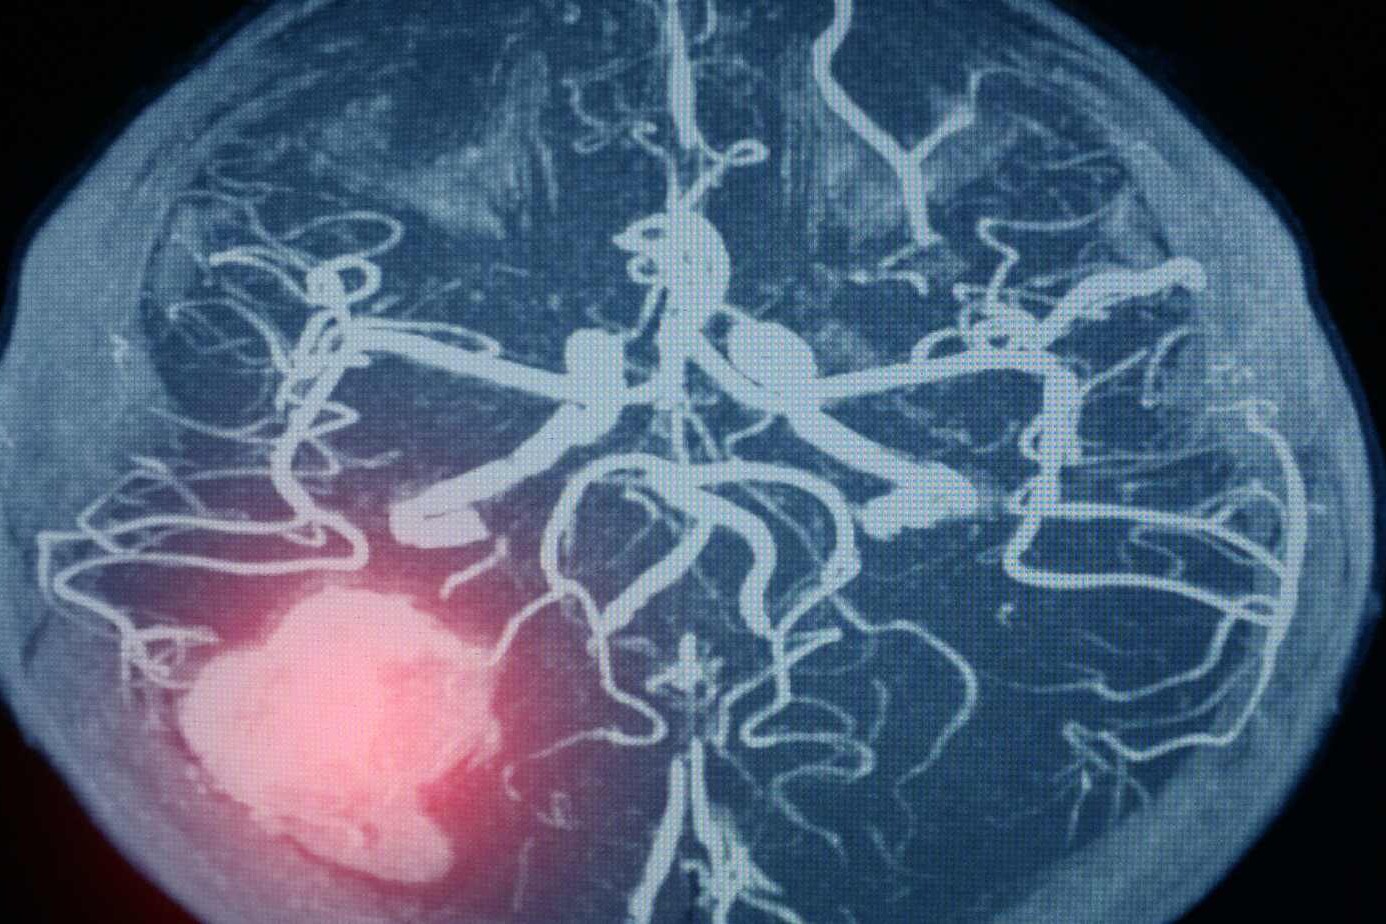

A Tiny Balloon in the Brain: Aneurysm is like a small balloon on the blood vessels in your brain. These vessels are like roads for blood to travel to different parts of your brain.

Where They Form: Aneurysms can pop up anywhere in the brain, but they mostly like to hang out at the junctions where blood vessels split or bend. It’s like how a garden hose might bulge at a kink or a split.

- Cerebral Angiogram: This is a more detailed test. Doctors insert a thin tube into a blood vessel, usually in the leg, and guide it up to the brain. Then, they inject a special dye that shows up on X-rays. It’s like drawing a map of all the blood vessels in your brain so doctors can spot any aneurysms.

- MRA (Magnetic Resonance Angiography): This is a special type of MRI that focuses specifically on blood vessels. It’s like having a zoomed-in view of the highways in your brain to check for traffic jams or bulges.